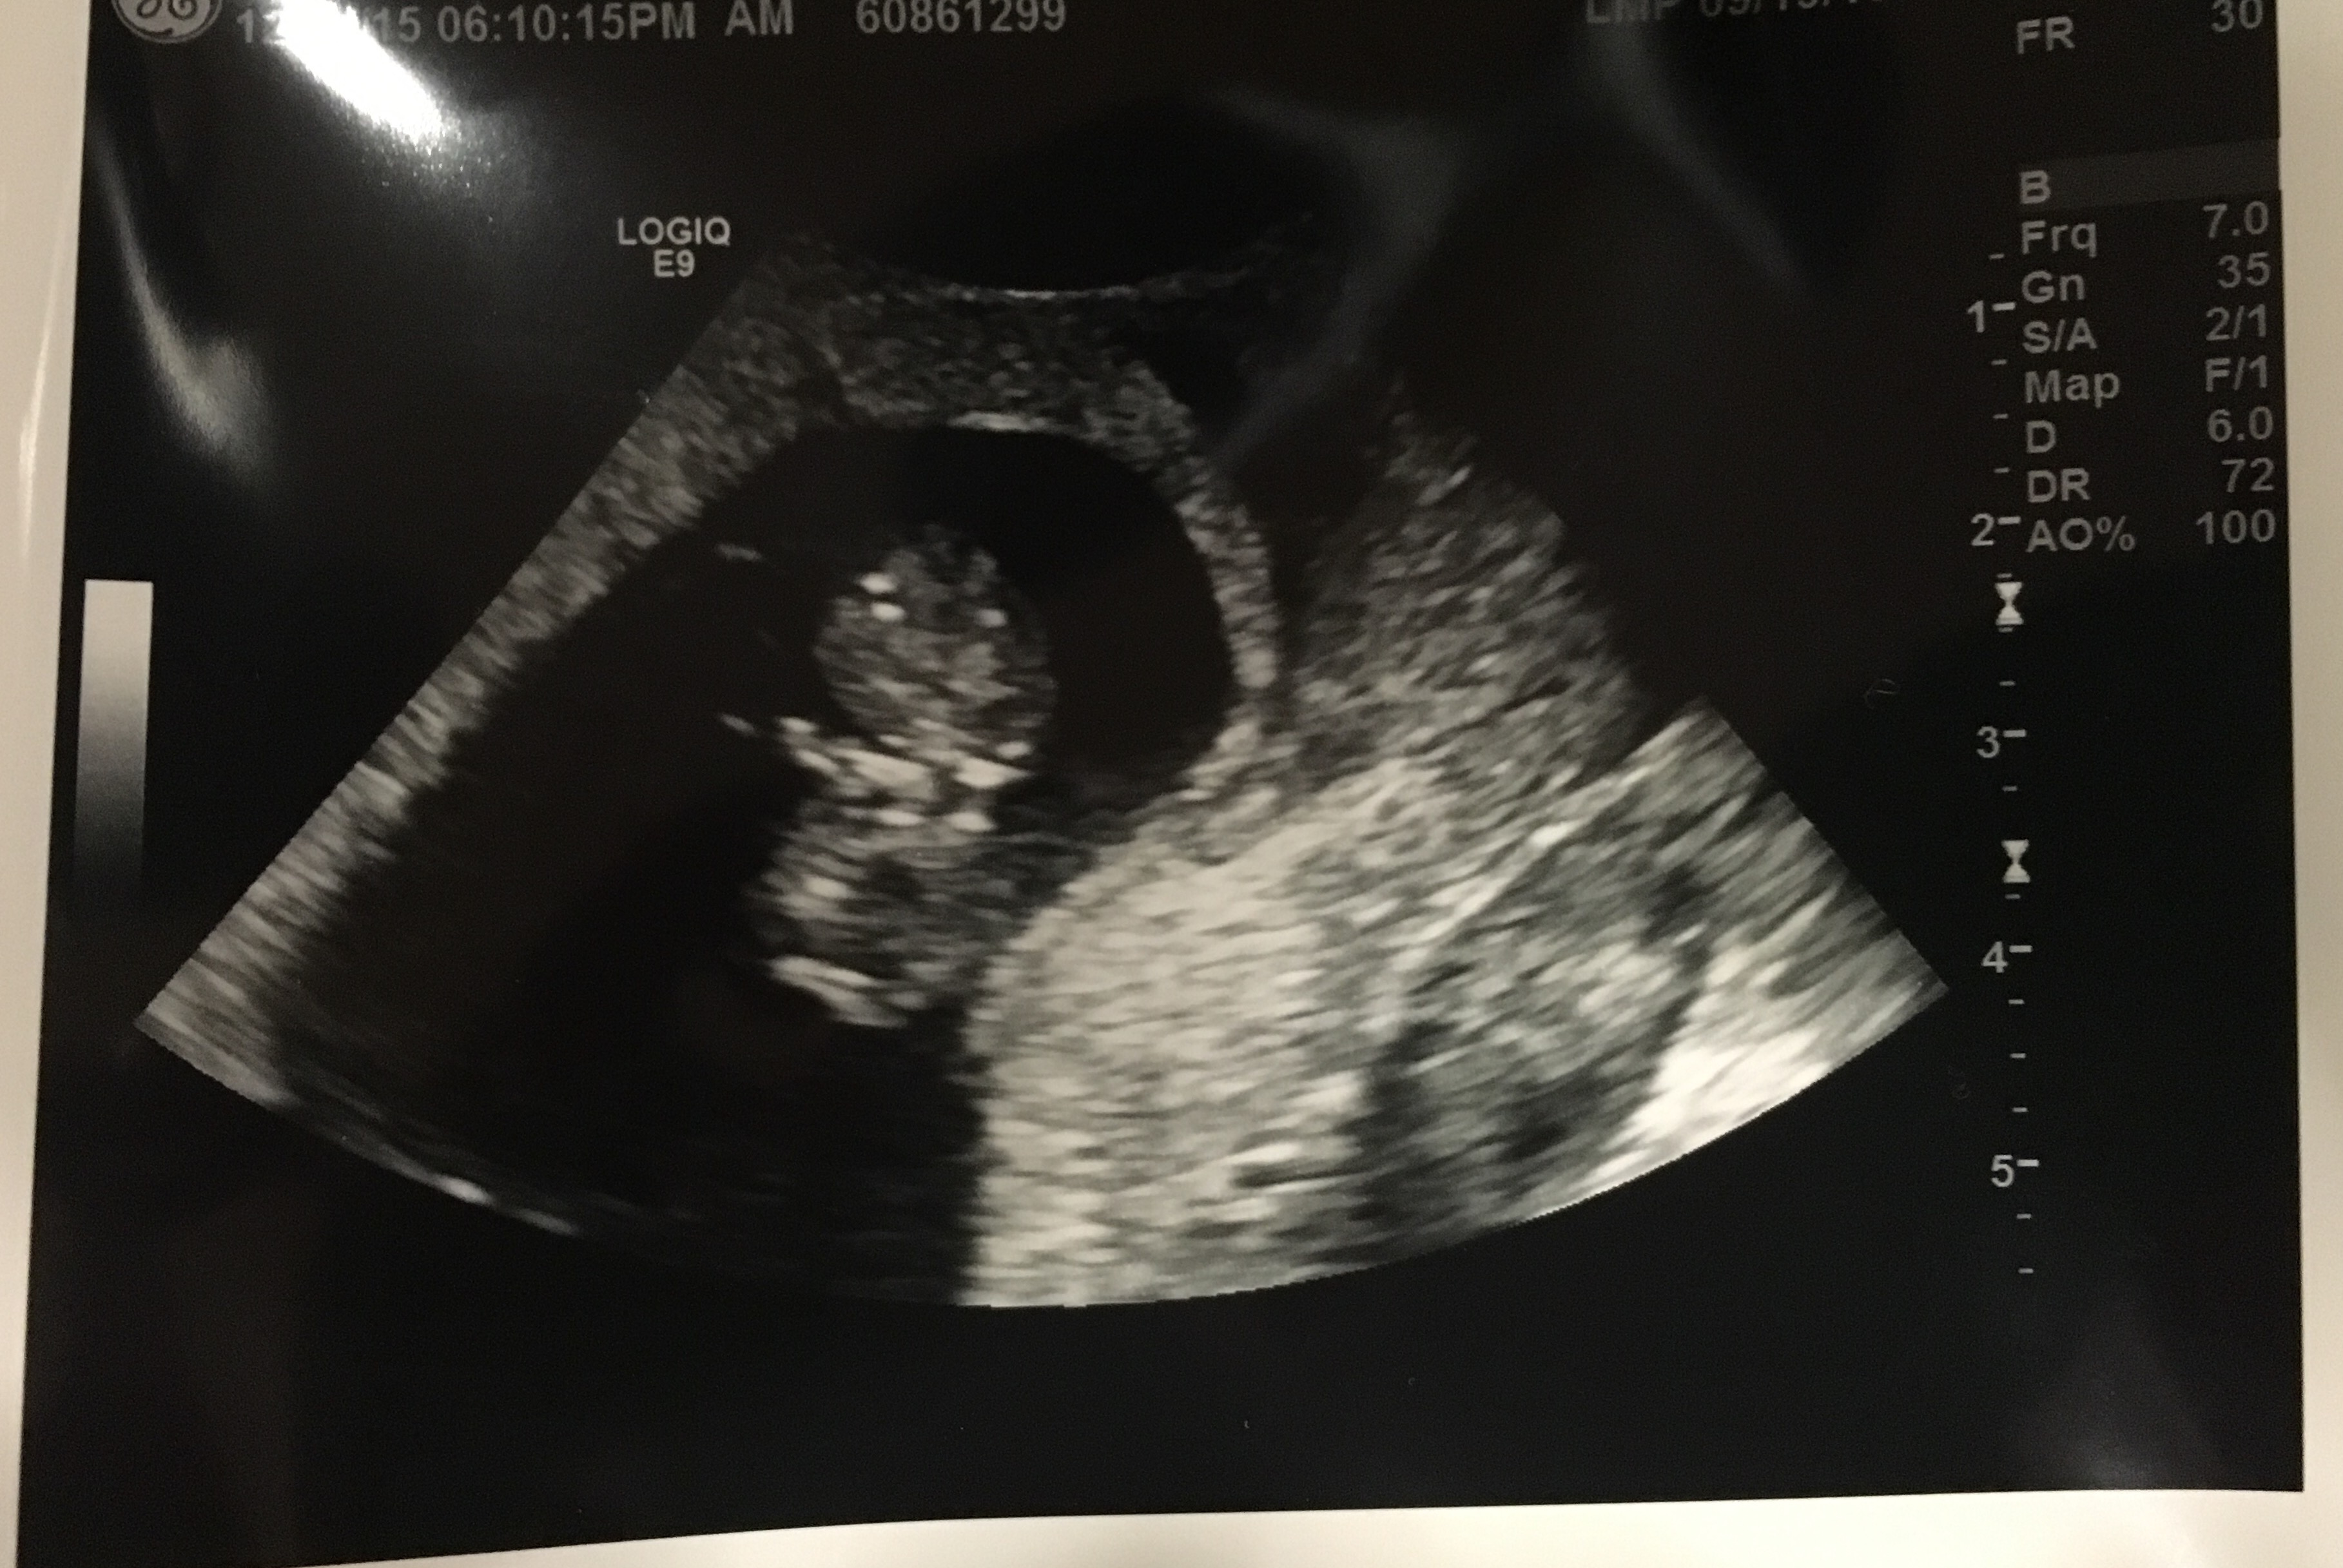

My first ultrasound pic at 9w3d. Measured a few days small. Doctor pointed out that I had twins, but one was not able to stick around We're sad about this, but we're thrilled to see our other healthy little baby! So in love!